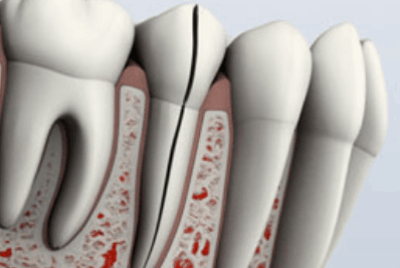

Diente fisurado tratable

Este tipo de fisura se extiende desde la superficie de masticación del diente y migra verticalmente hacia la raíz. En algunos casos, la grieta puede extenderse por debajo de la línea de las encías. Es posible que la grieta se extienda más hacia la raíz. El daño a la pulpa es común. En este caso, el tratamiento del conducto radicular suele ser necesario. Un diente roto que no se trata empeorará, lo que provocará la pérdida del diente. Por lo tanto, la detección temprana es esencial.

Diente partido:

Un diente partido suele ser el resultado de un diente fisurado no tratado. Se puede identificar por una grieta con segmentos distintos. Este tipo de diente nunca se puede salvar intacto. Sin embargo, la posición y el alcance del problema determinarán si se puede salvar alguna parte del diente. A veces, el tratamiento endodóntico y la restauración por parte de su dentista se pueden salvar una porción del diente.